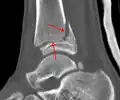

A triplane fracture of the ankle as seen on CT

CT

CT scans may be indicated when there is concern for a highly comminuted fracture or a fracture involving the joint surface.[9] This imaging may be used for surgical planning.

- Triplane fractures are a special type of fracture that involves the immature skeleton. It has a coronal plane in the metaphysis, an axial plane in the physis, and a sagittal plane in the epiphysis.[14]